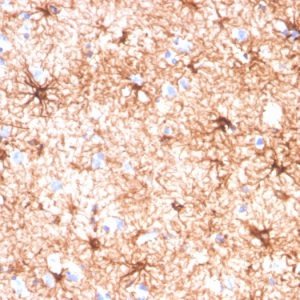

Antibodies against GFAP are widely used in research and diagnostics. Immunohistochemistry and immunofluorescence techniques employing anti-GFAP antibodies help identify and visualize astrocytes in tissue sections. Clinical applications of measuring its levels include its use as a biomarker for diagnosing and monitoring traumatic brain injury.

Glial Fibrillary Acidic Protein (GFAP) has a molecular weight of approximately 50 kDa. It is primarily expressed in astrocytes, a glial cell in the central nervous system (CNS), and a marker for mature astrocytes. It is crucial for the normal functioning of astrocytes, which play a role in various processes, including the maintenance of the blood-brain barrier, regulation of neurotransmitter levels, and response to injury. Increased levels of Glial Fibrillary Acidic Protein in the cerebrospinal fluid (CSF) or blood are associated with various CNS injuries and neurodegenerative diseases, including traumatic brain injury (TBI) and stroke.